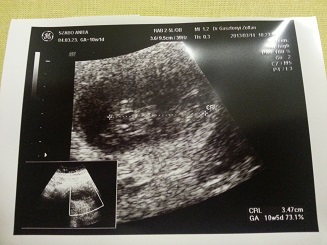

Ja, az ultrahangról én is úgy tudom, hogy a sima 2D-s se tesz jót a babának, pláne gyakran és hosszú ideig használva, a párom most volt egy erről szóló kongresszuson. A 4D pedig nagyságrendekkel nagyobb megterhelést jelent a magzatra, úgyhogy mi Áronnal sem voltunk és most a kicsivel sem megyünk ...